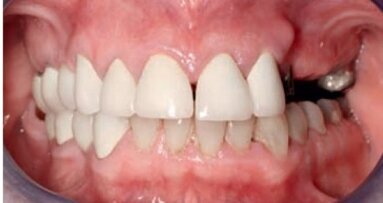

67-letnia pacjentka zgłosiła się do gabinetu stomatologicznego w celu konsultacji w sprawie leczenia implantologicznego. W wywiadzie zgłaszała pewne ...